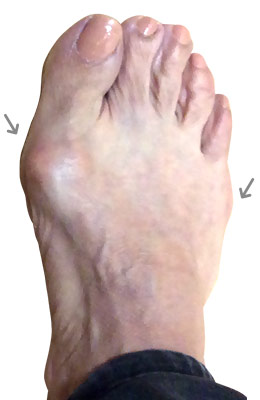

Before

Minimally Invasive Bunion Surgery featuring the CrossRoads miniBunion™ System before

After

Minimally Invasive Bunion Surgery featuring the CrossRoads miniBunion™ System after

Minimally Invasive Bunion Surgery featuring the CrossRoads miniBunion™ System

Eva is a 24-year-old female who had just began working at a job that required high fashion shoes. She was in constant pain but could not take time off work. Our miniBunion™ Minimally Invasive Bunionectomy allowed her to continue to work and be on her foot with full recovery and return to regular shoes by 6 weeks. She had an amazing range of motion, no more bunion pain, and absolutely no visible incision. After picture taken six weeks post-surgery.